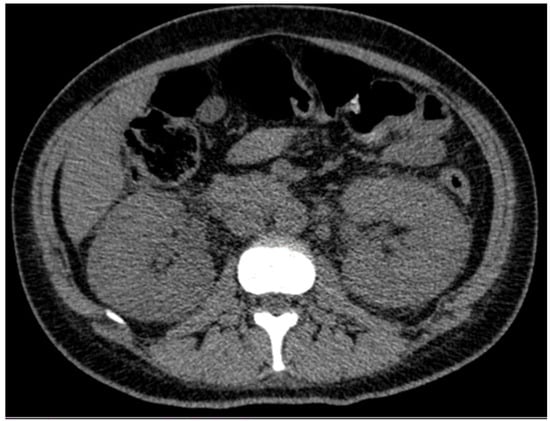

| Ultrasound (kidney size, in cm)  | RK = 12.4 LK = 13.3 | RK = 15.8 LK = 16 (day 25) + kidney biopsy (day 27)  | |||||